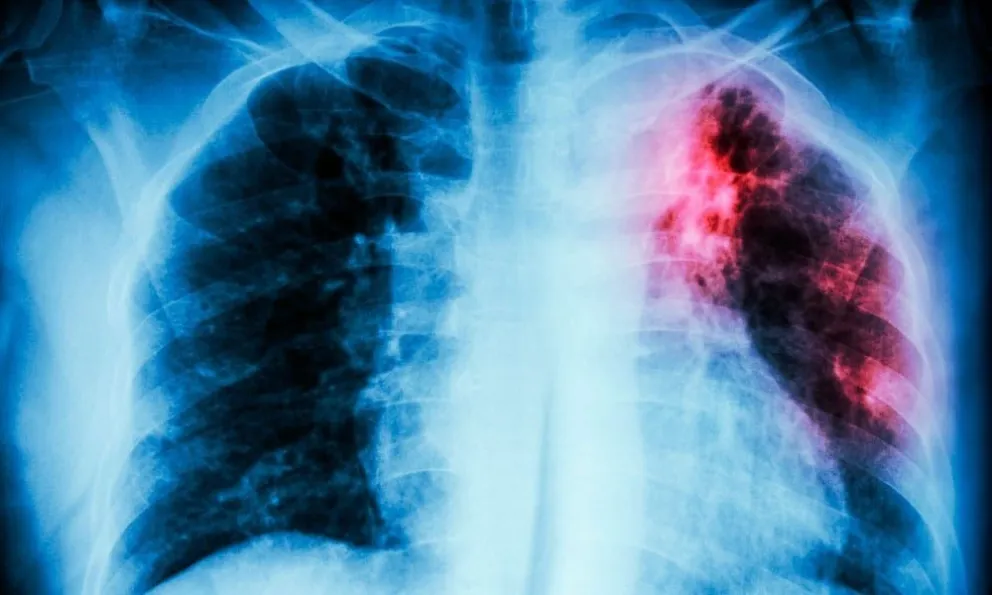

En el marco del Día Mundial de la Tuberculosis, que se conmemora cada año el 24 de marzo, desde el Ministerio de Salud Río Negro se destaca la importancia de pensar en esta enfermedad durante todo el año. Se trata de una enfermedad infecciosa cuya transmisión se produce fundamentalmente por vía área, mediante la bacteria Micobacterium tuberculosis y su llegada a los pulmones. Puede desarrollarse en cualquier órgano, pero la mayoría de las veces se localiza en los pulmones.